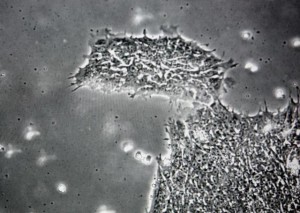

研究人員已經(jīng)發(fā)現(xiàn)了一種能夠?qū)е氯祟?lèi)認(rèn)知減退的藻類(lèi)病毒

據(jù)美國(guó)科學(xué)家稱(chēng),他們已經(jīng)發(fā)現(xiàn)了一種能夠影響人類(lèi)大腦并且使我們更愚蠢的病毒。這種藻類(lèi)病毒之前從未在健康人類(lèi)當(dāng)中發(fā)現(xiàn),科學(xué)家發(fā)現(xiàn)它能夠影響包括視覺(jué)處理和空間意識(shí)在內(nèi)的大腦認(rèn)知功能。

約翰-霍普金斯醫(yī)學(xué)院和內(nèi)布拉斯加大學(xué)的科學(xué)家們?cè)谶M(jìn)行一項(xiàng)咽喉微生物研究時(shí)偶然發(fā)現(xiàn)了這種病毒。令人驚奇的是,研究人員發(fā)現(xiàn)健康人群咽喉中的DNA與一種已知的綠藻類(lèi)病毒DNA相匹配。